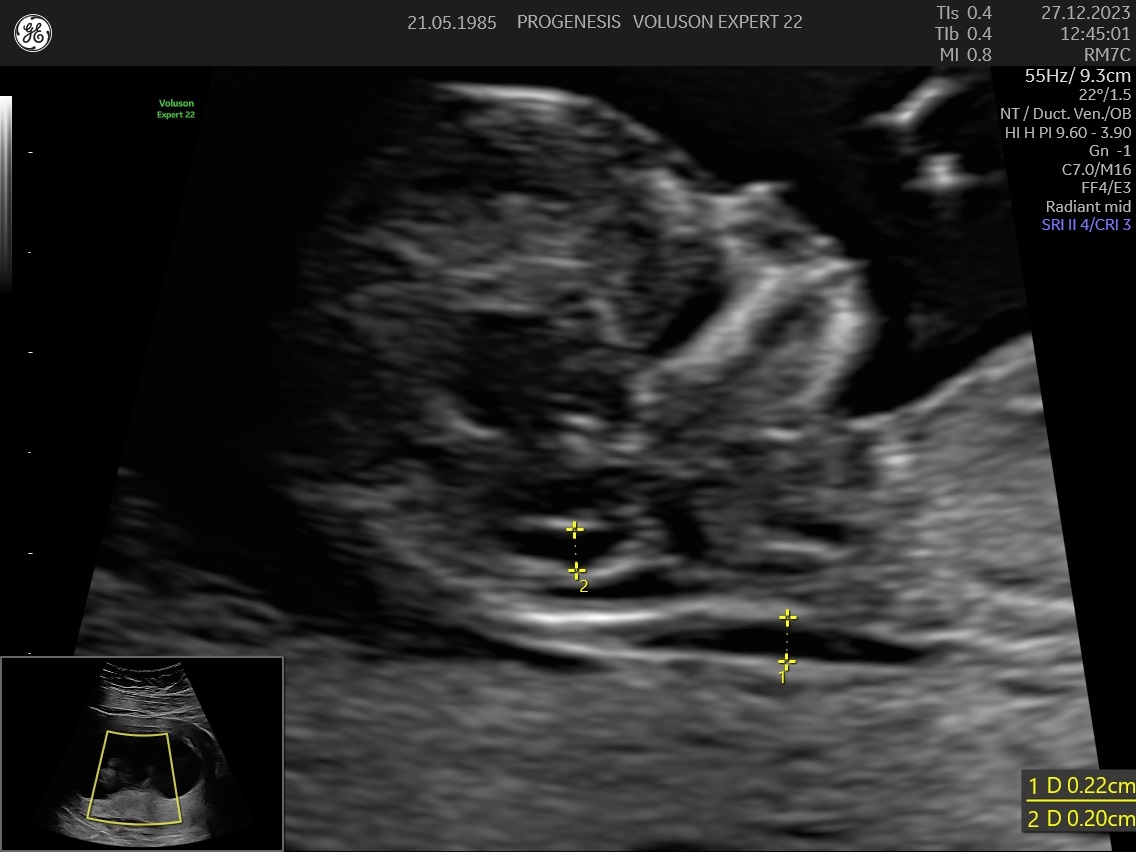

Πρώτη εκτίμηση πιθανότητας πρόωρου τοκετού και προεκλαμψίας

.Κατά τη διάρκεια της κύησης ο τράχηλος της μήτρας πρέπει να είναι μακρύς και κλειστός.

Μετρώντας το μήκος του, υπολογίζουμε την πιθανότητα για πρόωρο τοκετό <34 εβδομάδες. Αξιολογείται σε όλες τις εγκύους, αλλά είναι ιδιαίτερα χρήσιμο στις μητέρες με παράγοντες κινδύνου όπως ιστορικό αποβολών 2ου τριμήνου ή πρόωρου τοκετού, πολύδυμη κύηση, συγγενείς ανωμαλίες μήτρας, ιστορικό επεμβάσεων τραχήλου (κωνοειδή εκτομή, LLETZ)